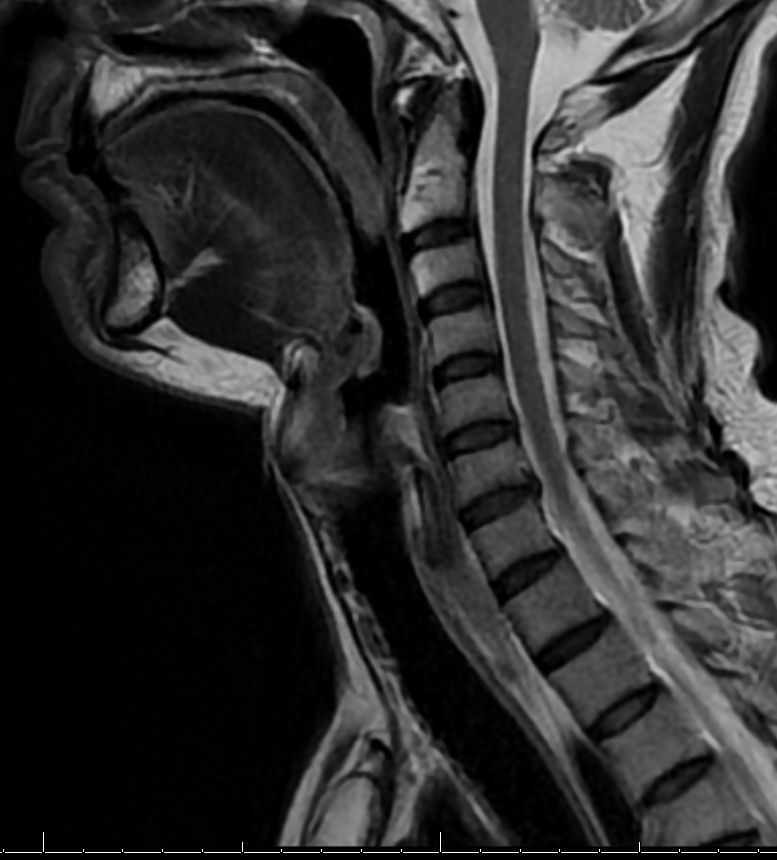

MRT: supraglottisch T3 No |

57-jähriger Mann mit langjährigem Alkohol- und Nikotinabusus. Seit 6 Monaten Schluckbeschwerden. Jetzt zunehmende Kachexie. MRT: Ausgedehntes supraglottisches Larynxkarzinom mit Schildkrorpel-Infiltration. Kehlkopfteilresektion mit ND. Histologie: unverhornendes Plattenepithelkarzinom, V0 R1 G1 - 2 Stadium post OP: pT3 pN0 (0/7) M0 | ||